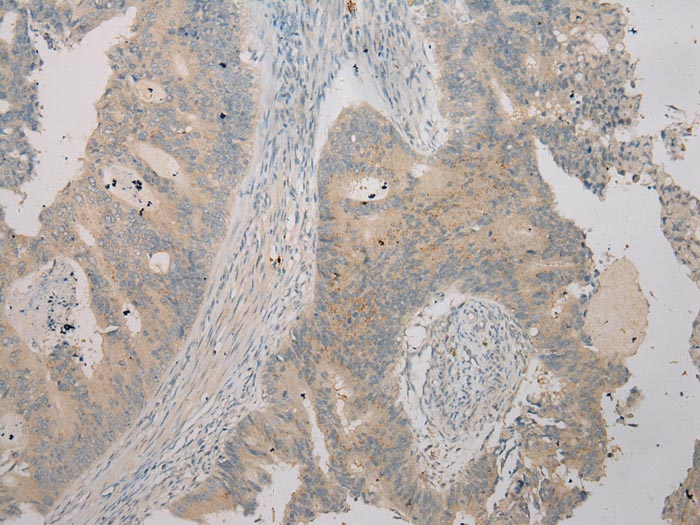

Immunohistochemical analysis of paraffin-embedded Human Colorectal cancer tissue using #40270 at dilution 1/100.